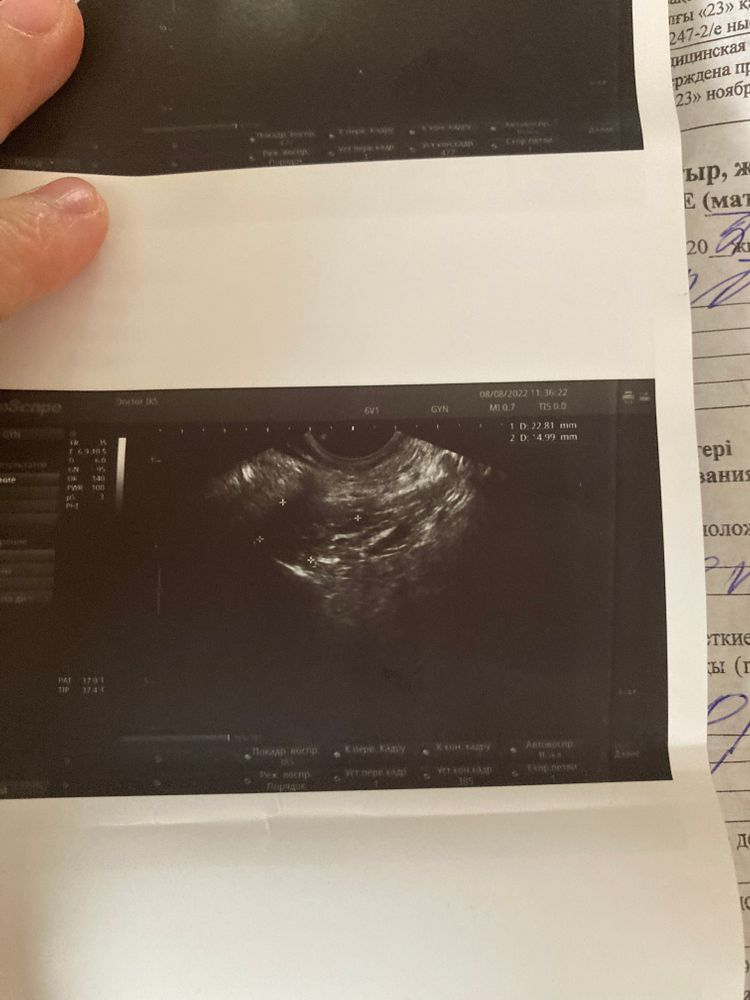

УЗИ на 19ДЦ Жидкость за маткой 3-4 дпо